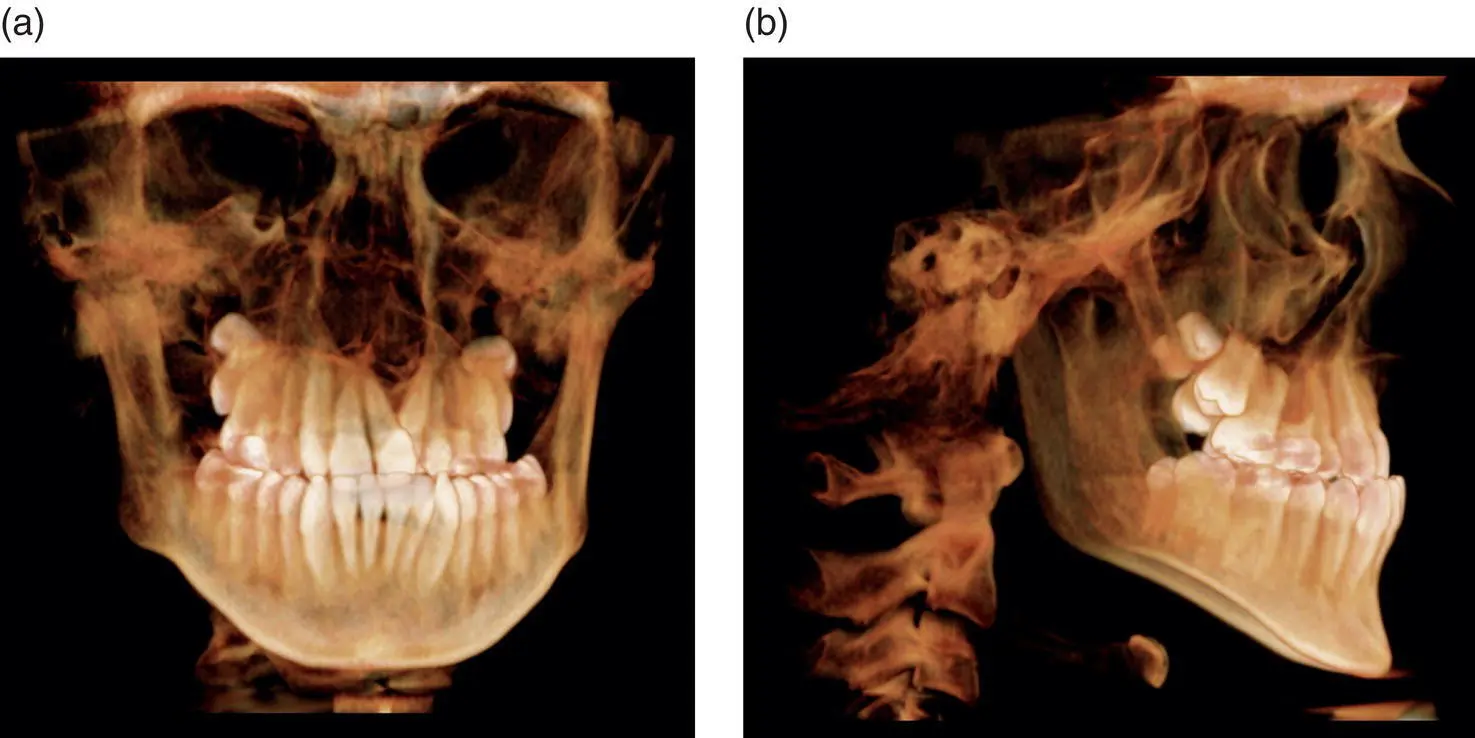

Figure 1.3.(a) 3D rendering of a medium FOV of 8 cm × 8 cm from an anteroposterior (AP) view. (b) 3D rendering of a medium FOV of 8 cm × 8 cm from a lateral view.